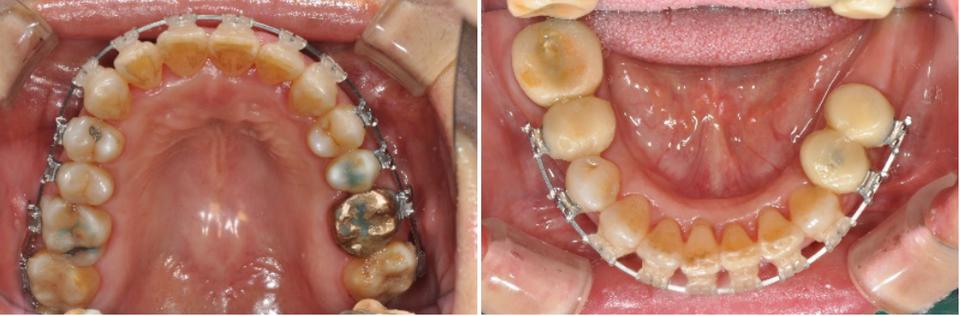

이 환자는 하악우측 제2대구치와 좌측 제1,2대구치가 결손된 환자로 하악 양측 distal cantilever 보철물 하방의 식편압입과 잇몸염증을 주소로 내원하였습니다. 또한 전치부의 crowding을 해결하기 위한 전악교정치료를 원하셨습니다.

하악구치의 cantilever 보철물을 제거하고 temporary crown으로 수복하여 bracket을 부착하였으며 결손부위는 일단 놔둔 상태에서 교정치료를 진행하였습니다.